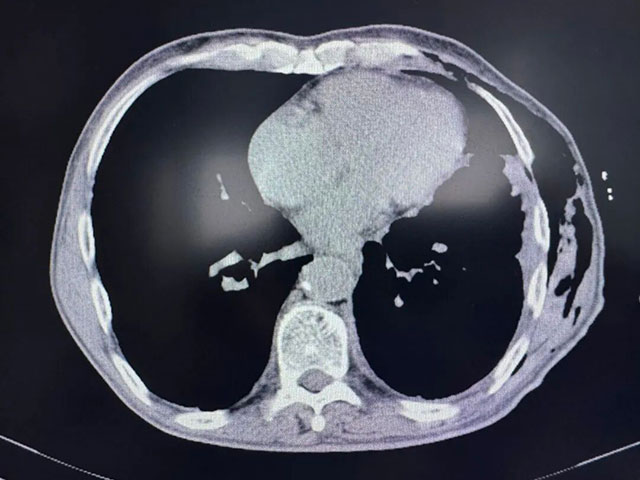

术后胸部CT

7月9日,刘浩副教授手术团队为张爷爷实施胸腔镜下肺部分切除术+胸腔积液清除术+胸膜活检,成功切除了1.5×1.1×1.0cm大小的浸润性腺癌病灶,并清除了胸腔内积液。术后病理提示,肿瘤已侵犯肺膜,属于晚期肺癌,治疗预后不佳。

“确定最佳药物剂量、灌注频率以及……”术后恢复一段时间后,7 月31日,张爷爷接受了关键的胸腔热灌注化疗(HITOC)。复查显示,各项指标平稳,仅红细胞略有下降,对症处理后迅速恢复。